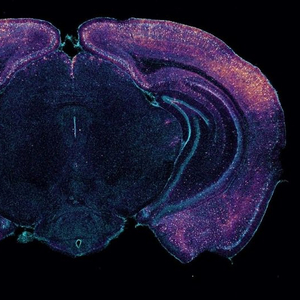

小鼠大脑的横截面,显示神经元似乎释放出能更好清除毒素的分子。

图片来源:《自然》网站